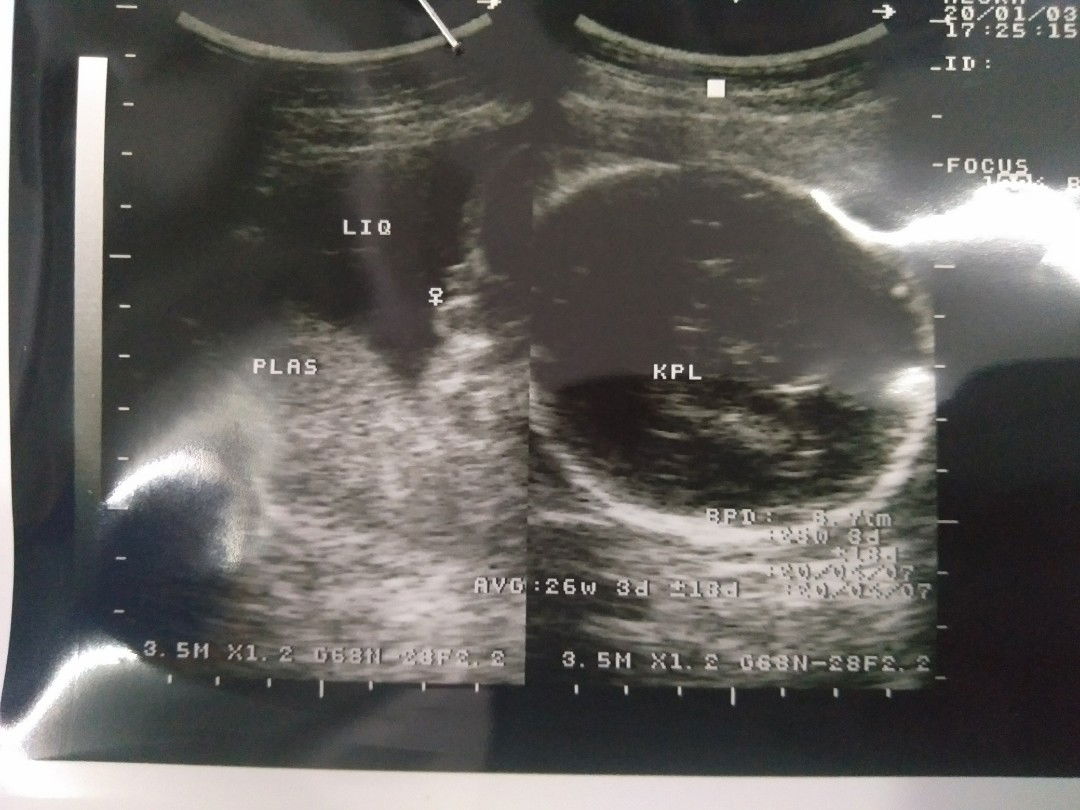

6 bulan

alhamdulillah sudah ketahuan jenis kelamin nya, setelah beberapa kali masih di sembunyikan ????. sehat sehat terus nak ❤❤❤❤